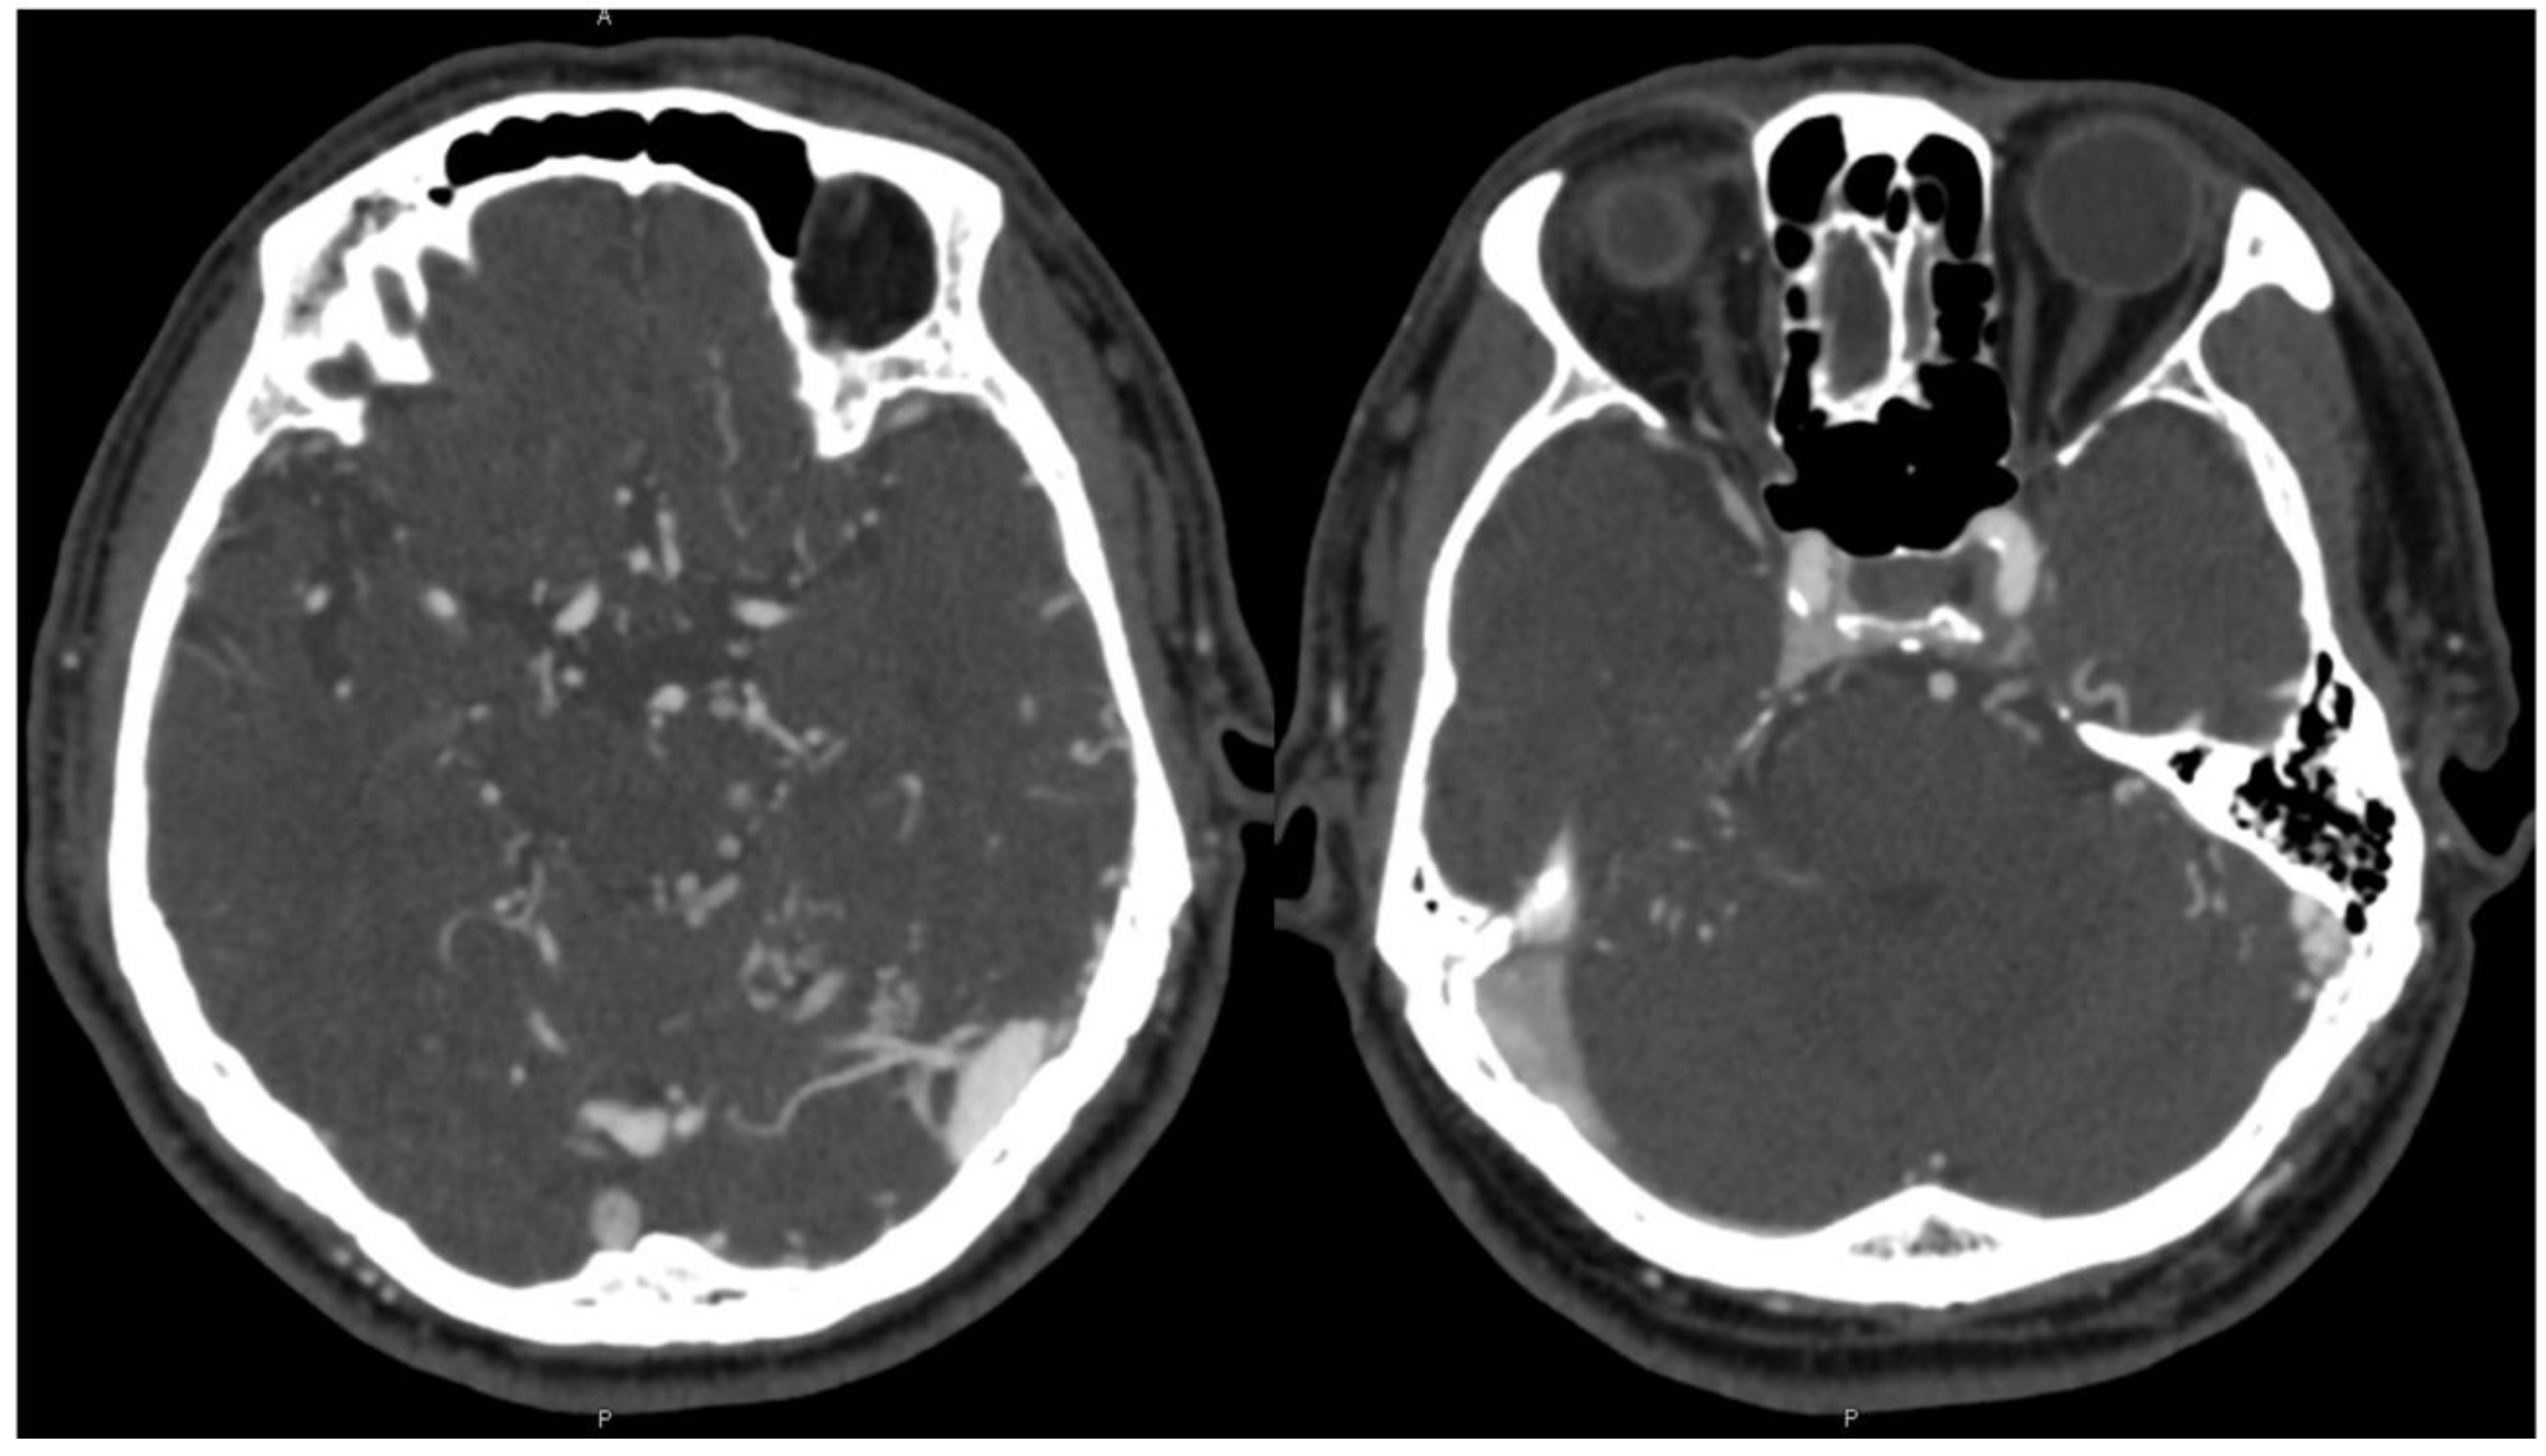

A 72-year-old male presented with the primary complaint of persistent headache for two months. Additionally, he complained of gradually progressing “brain fog” and fatigue over the course of several years. There was also left-sided pulsatile tinnitus that subtly existed over several years but worsened in the preceding two months. CT and CTA head and neck were obtained, which showed possible early filling of the right cavernous sinus, increased vascularity around the left sigmoid–transverse sinus junction, and dilated bilateral cortical veins, more notable on the left (Figure 1). The patient was recommended to undergo cerebral angiography which revealed a Borden II/Cognard IIa+b DAVF (Figure 2).

Figure 1. CTA demonstrated early filling of the right cavernous sinus, increased vascularity around the left sigmoid–transverse sinus junction, and dilated bilateral cortical veins, more notable on the left.